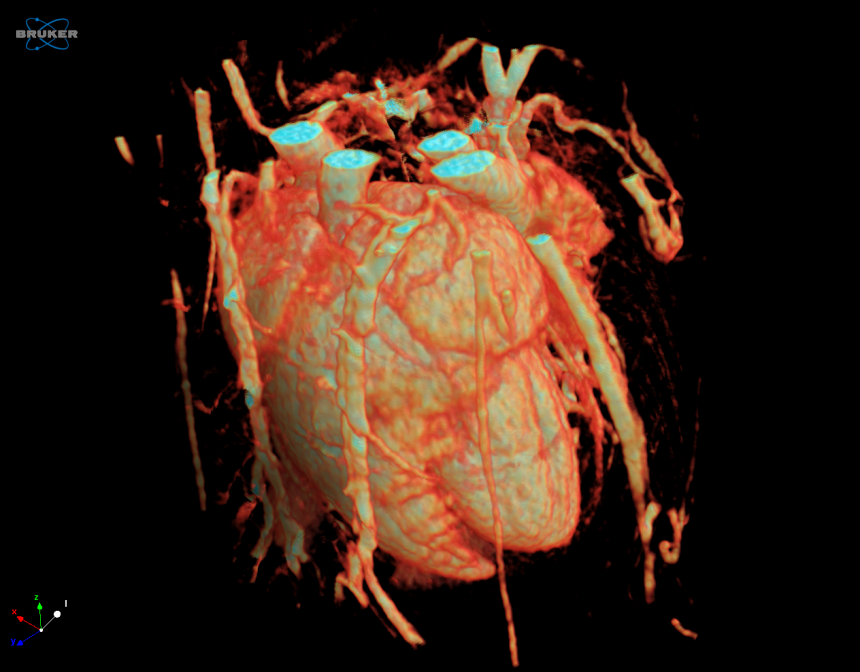

Cardiovascular Applications

The SKYSCAN 1278 is a versatile cardiac imaging solution for both mouse and rat. The rat heart and lungs are imaged in a single scan FOV thanks to the large and fast cMOS flat panel x-ray camera. The scanner and accompanying software provide sharply time-gated cardiac, lung and dual (cardiac-lung gated) images in short scan times with safe levels of ionizing radiation. As with all SKYSCAN in vivo scanners, physiological monitoring is at the heart of the instrument, with the welfare of the animal the top priority.

- Full in-house software solution for cardiac function analysis in 4D: ejection volume, other cardiac chambers and aorta, time-analysis of cardiac wave-train including regularity and fractality, with flexible segmentation and analysis of the cardiac cycle in CT-Analyser software.